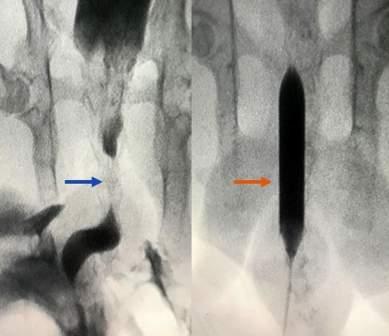

During and after the 90 days of radiotherapy, we observed 29 6% grade 1-2 genitourinary (GU) and gastrointestinal (GI) toxicity, and one patient (3 7%) presented grade 3 acute GI toxicity exacerbated by an abscess treated surgically (Table 4)

Late toxicity

We observed 14 8% (n = 4) grade 2 late urinary toxicity, including urethral stricture resolved by drilling in 11 1% of patients and haematuria related to bladder cancer in one patient No late GI toxicity was detected (Table 4)